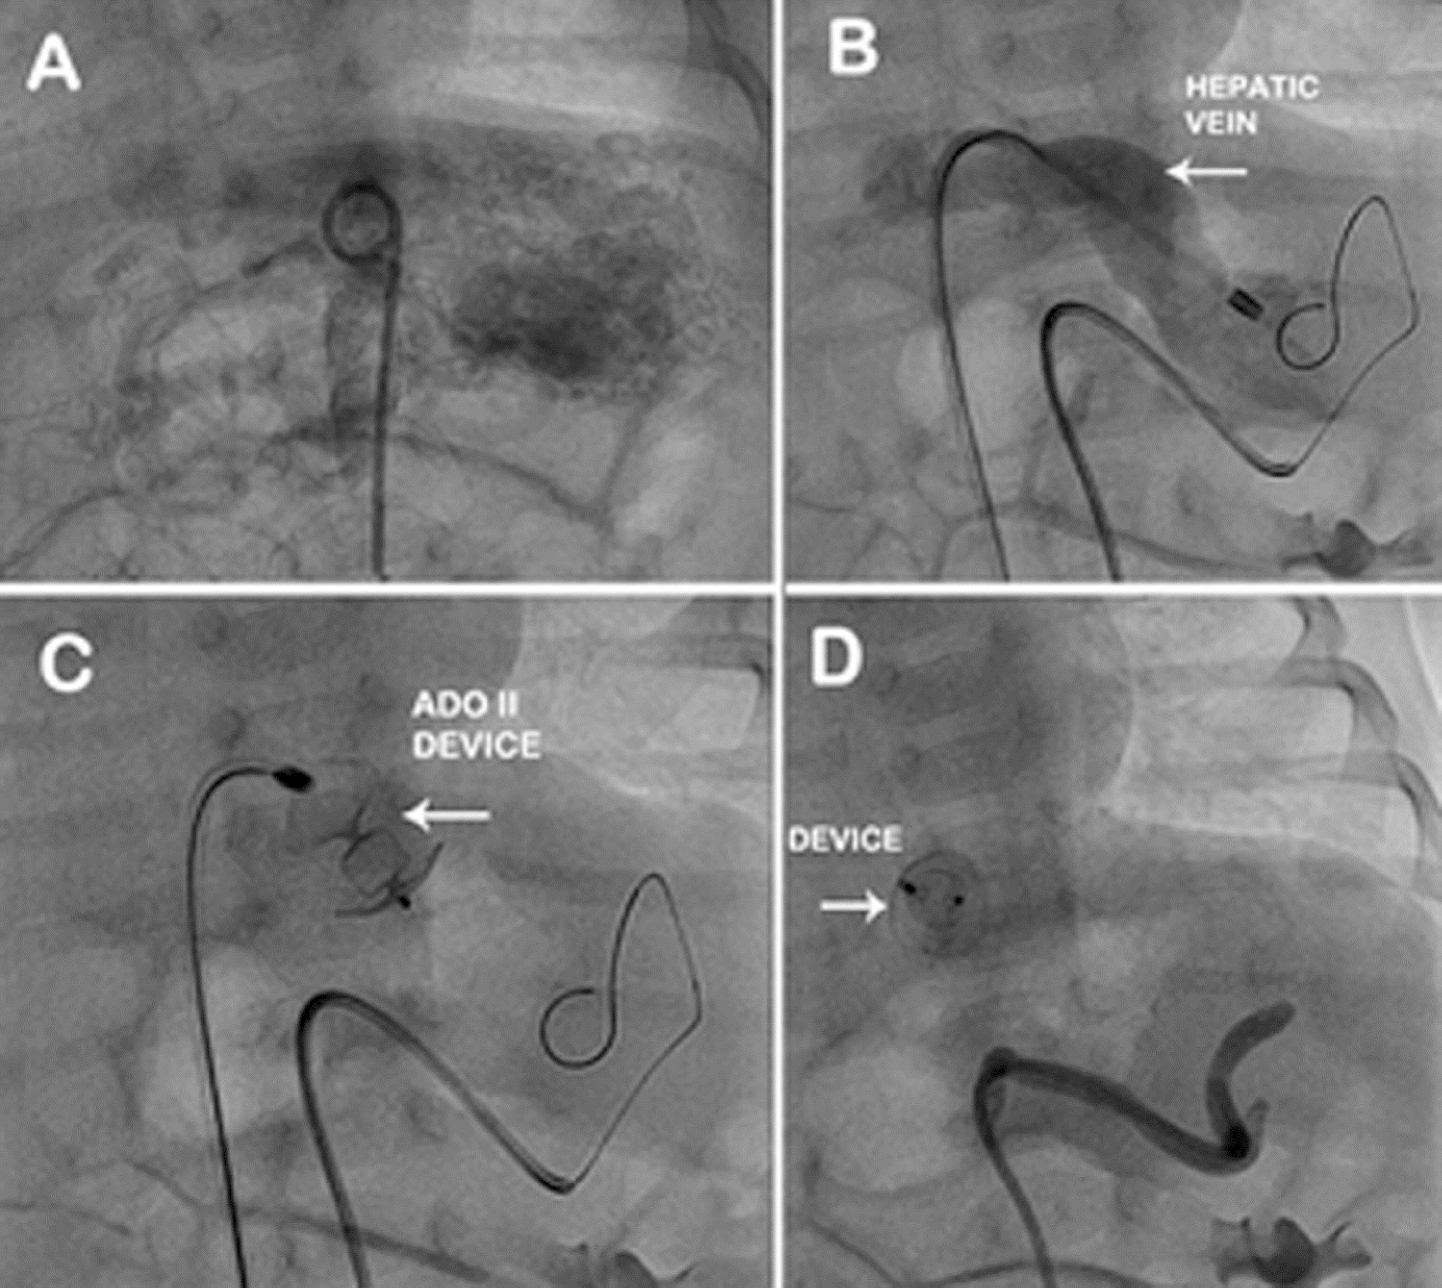

The procedure was done on 40th day of life. Both left and right heart catheterization was done through right femoral artery and vein by Seldinger’s technique under epidural anesthesia and intravenous ketamine. The descending aorta angiogram done in anterioposterior view with 4F pigtail catheter showed highly vascular lesion, fed through the celiac plexus draining into grossly dilated (10 mm) hepatic vein (Fig. 2A). Then with 4F Judkins right coronary artery (RCA) catheter, selective angiogram was done to identify the feeders. There were two feeders. The bigger of the two arteries with circuitous course was supplying the major portion of the mass. The lesion was entered using 0.018” x 260 cms Terumo guide wire and 4F Terumo catheter was passed over the wire, well into the middle of the lesion. Through the venous sheath, 0.018” x260cms Terumo guide was passed into the dilated hepatic vein. Over this curved Cooks 4F shuttle sheath was inserted into the hepatic vein (Fig. 2B). Then through the shuttle sheath, 6 x 6 ADO II device (St Jude Medical, Minnesota) was deployed at the bend of the vessel, but not released (Fig. 2C ). The grated gel foam particles mixed with diluted contrast were injected from the arterial end through 4F

Terumo catheter. Almost complete cessation of flow through the anomalous channel was achieved by instillation of PVC particles at the end. The care was taken so that the diluted contrast containing PVC particles did not reflux into the celiac plexus. Once the check angiogram showed good occlusion of the mass, the ADO II device was released. Post procedure angiogram showed no flow into the hepatic lesion from the arterial end and the device was in good position at the venous end (Fig. 2D). The highly vascular lesion before procedure (Fig. 3A) regressed completely post procedure with the device in situ (Fig. 3B). The patient developed distension of upper abdomen after the procedure. This was treated conservatively as peristaltic sounds were well heard and the patient recovered within 48 hours. Post procedure there was also a local complication with loss of pulse in right femoral artery. This was treated with intravenous heparin infusion for 24 hours followed by intravenous heparin 8th hourly for 72 hour, till the pulse was well felt and there were good Doppler signals. This led to reappearance of vascular channels in the lesion on abdominal ultrasound. But the CT angiogram done after 3 months showed significant reduction in the size of the mass from 58x29x50 mm (before procedure) to 25 x 10 x 20 mm (Fig. 4A and B). The child has gained weight (5.25kgs), review echocardiogram showed hyper echogenic healed vegetations, not mobile and EF improved to 55%.

Fig. 2A. Abdominal aortogram with pig tail catheter shows IHH.B: 4 F Terumo catheter with the Terumo guide wire in the mass and 4 F Cooks shuttle sheath through inferior vena cava into dilated left hepatic vein. C: Amplatzer Duct Occluder II device with two retention discs and middle lobe parked in the hepatic vein. D: Check angiogram shows complete occlusion of IHH with Amplatzer Duct Occluder II in situ